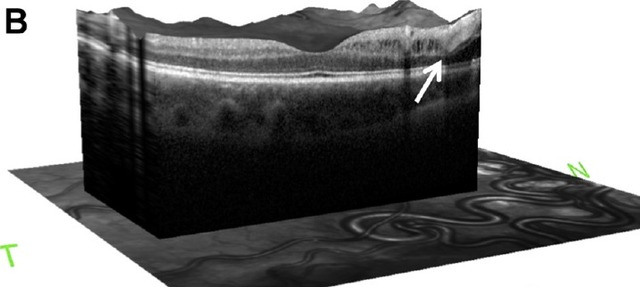

患者,男,6 岁,右眼视力光感,瞳孔对光反应缺陷,眼底照相显示扩张扭曲的眼底血管(图 A)。OCT 显示视乳头与黄斑间的视网膜下层有积液层(图 B 箭头处)。MRI 图像显示视神经管或眶尖有增强(图 C 箭头处),在后眼眶匍匐的小血管有流空现象(图 D 箭头处)。这些眼部与脑部的病理变化与 Wyburn-Mason 综合征有关。

图 B 为患者 OCT 图像